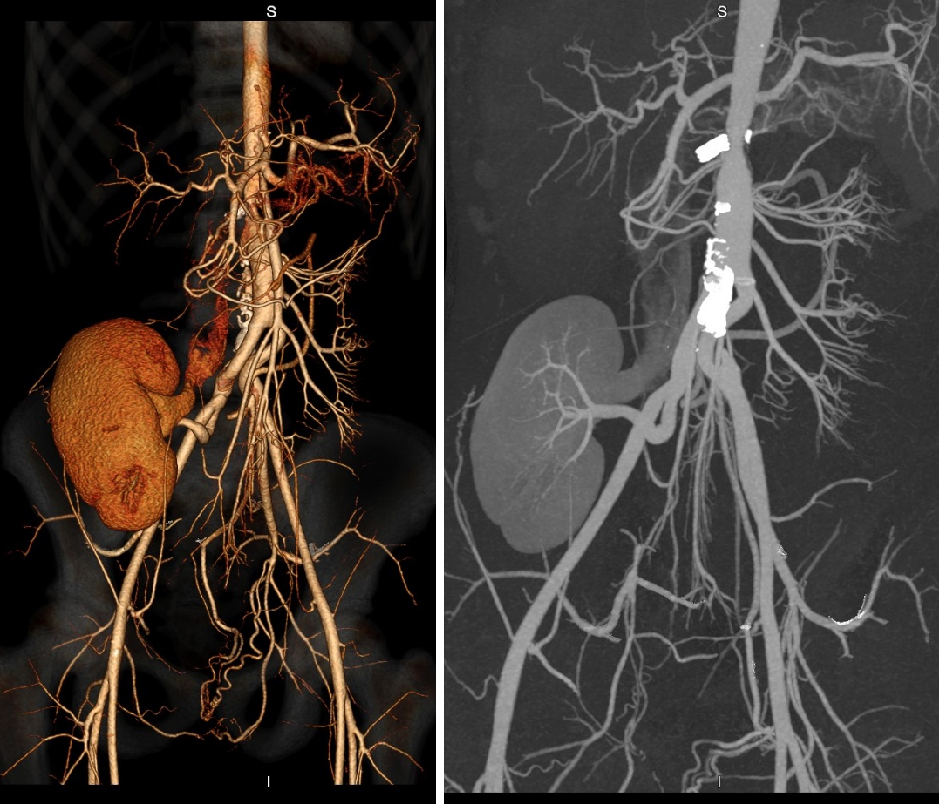

肾动脉狭窄:肾动脉重建

16岁,纤维肌性发育不良(FMD)

左肾动脉一级分支多发狭窄(3处)

左髂内动脉 Graft 重建左肾动脉,移植于左髂窝

21岁,纤维肌性发育不良(FMD)

左肾动脉、副肾动脉全程狭窄,其中一支合并动脉瘤

采用左髂内动脉重建左肾动脉,移植于左髂窝